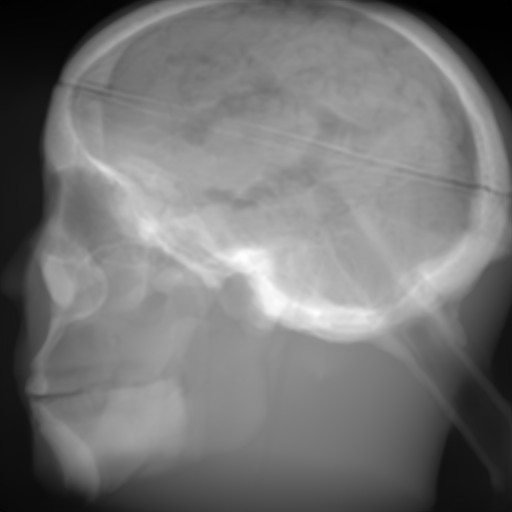

(a) Input: MR proj.

(b) Output: U-net p-loss.

(c) Output: ResNet p-loss.

(d) Output: CRN p-loss.

(e) Reference: X-ray proj.

Figure 2: Results of the projection synthesis. Top row: Results generated with the perceptual-loss function. Bottom row: Results generated with the 1subscript1\ell_{1}-loss function.

The quantitative and qualitative results of the proposed experiments are presented in Table I and Figure 2. By examining these it can be observed that the differences in the calculated MSE of all network architectures and incorporated loss functions are only small. The best results in terms of pixel-wise deviation could be achieved with the ResNet architecture combined with the 1subscript1\ell_{1}-loss function. This network achieves a deviation from the reference of only 0.058, i.e., 2.4 percent. Also the results of the U-net and CRN networks are still good with deviations of 2.6 and 2.9 percent. Similarly small variation can be observed in the structured similarity measure. The ResNet and CRN exhibit approximately equal quality with SSIM measures of 0.938 and 0.920 for the 1subscript1\ell_{1}-loss and 0.924 and 0.931 for the perceptual-loss, respectively. The results generated with the U-net are slightly worse. The highest peak signal-to-noise ratio is achieved by the ResNet (1subscript1\ell_{1}-loss), followed by the U-net (1subscript1\ell_{1}-loss) and CRN (p-loss). It is noteworthy that the ResNet and U-net both achieve the highest results in all error metrics using the 1subscript1\ell_{1}-loss while the opposite is the case for the CRN which works best with the perceptual-loss function.

Overall, the perceptual-loss achieves competitive and in some cases even better results than the 1subscript1\ell_{1}-loss when comparing the pixel-wise error metrics. For example, the cascaded refinement network’s MSE is 0.013 smaller for the perceptual- than for the 1subscript1\ell_{1}-loss. This might be suspicious at first sight, considering that the 1subscript1\ell_{1}-loss purely optimizes for this pixel-wise error in the training process while the perceptual-loss compares the raw feature activations of the evaluation network. Contrarily, this behavior cannot be observed for the U-net and ResNet. The results produced with the 1subscript1\ell_{1}-loss achieve higher values for all error measures for these networks. An explanation for this obervation is that the intensity values of the input image still cause an impact on the respective layers output in the evaluation network when computing the perceptual-loss. Consequently, these differences also transition to the computed loss value for all feature layers. Even though the perceptual-loss incorporates the raw intensity values, it is not guaranteed that the scaling of these is conserved in this process. By this, the relative changes can be similar, whereas the absolute range of values changes and, correspondingly, also the pixel-wise error metrics.

Another observation is that the perceptual-loss is able to conserve high-frequency details in the image. The fine line in the projection images that forms a circle around the cranium is visible in the input (Figures 2a & 2f), as well as in the label images (Figures 2e & 2j), and also in the images generated with the perceptual-loss function (Figures 2b2c, and 2d). In contrast, all generators ”loose” this line when the 11\ell 1-loss is applied (Figures 2g2h, and 2i). This effect is also qualitatively observable in other parts of the images. Despite achieving equal or better results regarding the error metrics, the generally less sharp look of the results generated with the 11\ell 1-loss function is apparent. This behavior is in accordance with previous observations that concluded that an perceptual-loss leads to sharper images than a comparable 11\ell 1-loss [19]. Considering the common applications of X-ray Fluoroscopy, e.g., interventional guidance for stents and similar devices, high spatial resolution is a key requirement. Utilizing a loss function that is able to preserve high-frequency details in the images is desirable to this end. The perceptual-loss appears to be suited for this task as presented in our evaluation.